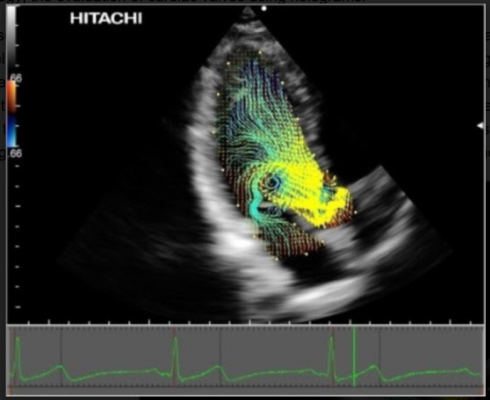

The presentation centered around Sengupta’s focus on discovering advanced visualization technologies to evaluate valvular form and function and how it is linked to the cardiac flow geometry. Some of his past work has been with particle image velocimetry (PIV) to demonstrate the valvular flow with vector information. He shared how he is now also using ultrasound to provide the vector information to evaluate this same flow geometry. He presented examples of PIV and Hitachi’s Vector Flow Mapping (VFM) analysis results side by side to illustrate the validity of ultrasound as a tool for vector mapping.

As a look into the future, Sengupta then demonstrated how holograms will play a part in valvular and other cardiac diagnosis by showing an example of a mitral valve hologram.